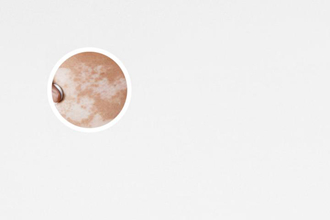

我們需要明確一點(diǎn):白點(diǎn)癲風(fēng)不是白癜風(fēng)疾病。白點(diǎn)癲風(fēng)是指皮膚上出現(xiàn)的白色斑點(diǎn),通常是由于皮膚內(nèi)的色素沉著不均勻所致。而白癜風(fēng)則是一種自身免疫性疾病,與遺傳因素有關(guān)。所以,在回答白點(diǎn)癲風(fēng)是否會(huì)遺傳給下一代的問(wèn)題時(shí),我們需要明確疾病的范疇。

根據(jù)目前的調(diào)查和醫(yī)學(xué)觀察,白點(diǎn)癲風(fēng)并不是一種遺傳疾病。多數(shù)情況下,白點(diǎn)癲風(fēng)是由于外界刺激、長(zhǎng)期緊張、免疫功能失調(diào)等因素引起的。而且,白點(diǎn)癲風(fēng)與個(gè)體的生活方式、環(huán)境因素等也有一些關(guān)系。因此,它不會(huì)直接遺傳給子女。